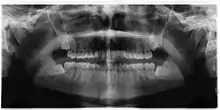

| Diagnostic method | Examination, x-ray |

Impacted wisdom teeth are classified by their direction of impaction, their depth compared to the biting surface of adjacent teeth and the amount of the tooth's crown that extends through gum tissue or bone. Impacted wisdom teeth can also be classified by the presence or absence of symptoms and disease. Screening for the presence of wisdom teeth often begins in late adolescence when a partially developed tooth may become impacted. Screening commonly includes a clinical examination as well as x-rays such as panoramic radiographs.

If the tooth cannot be assessed with clinical exam alone, the diagnosis is made using either a panoramic radiograph or cone-beam CT. Where unerupted wisdom teeth still have eruption potential several predictors are used to determine the chance of the teeth becoming impacted. The ratio of space between the tooth crown length and the amount of space available, the angle of the teeth compared to the other teeth are the two most commonly used predictors, with the space ratio being the most accurate. Despite the capacity for movement into early adulthood, the likelihood that the tooth will become impacted can be predicted when the ratio of space available to the length of the crown of the tooth is under 1.[5]: 141

There is no standard to screen for wisdom teeth. It has been suggested, absent evidence to support routinely retaining or removing wisdom teeth, that evaluation with panoramic radiograph, starting between the ages of 16 and 25 be completed every 3 years. Once there is the possibility of the teeth developing disease, then a discussion about the operative risks versus long-term risk of retention with an oral and maxillofacial surgeon or other clinician trained to evaluate wisdom teeth is recommended. These recommendations are based on expert opinion level evidence.[19] Screening at a younger age may be required if the second molars (the "12-year molars") fail to erupt as ectopic positioning of the wisdom teeth can prevent their eruption. Radiographs can be avoided if the majority of the tooth is visible in the mouth.